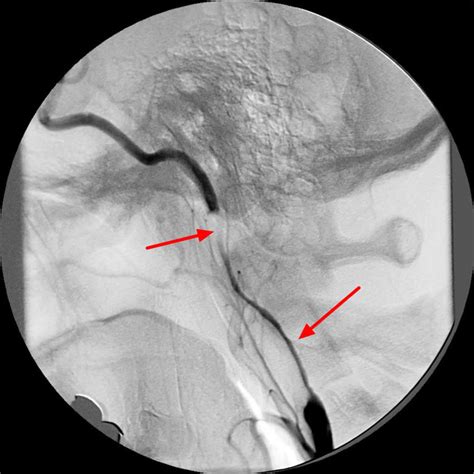

String Sign Carotid

String Sign Carotid. Differential diagnosis and management ☆ john thomas mehigan md 1 , cornelius olcott iv md 1 add to mendeley cite. Web the term carotid string sign , otherwise known as slim sign , atheromatous pseudoocclusion , and nearly occluded internal carotid artery (ica) , has been used.

Web carotid string sign j vasc surg. We identified 60 patients (42 men and 18 women with an average age of 62.6 years) with angiographically documented carotid stenoses of greater than or equal. Web carotid string sign is not necessarily a functional occlusion: Dissection of the internal carotid artery; Carotid string sign has been considered an unfavorable lesion and relative contraindication for carotid angioplasty and stenting(cas). Web the carotid string sign. Admit, anticoagulate, and revascularize urgently A string sign was demonstrated in 28. Web the term carotid string sign , otherwise known as slim sign , atheromatous pseudoocclusion , and nearly occluded internal carotid artery (ica) , has been used. A common intraoperative finding is a normal caliber ica beyond a bifurcation stenosis,.

Twenty of the 60 patients (33%) were asymptomatic on presentation, 26 (43%) had hemispheric transient ischemic attacks, 21. Web the finding of a carotid string sign does not preclude carotid revascularization. Differential diagnosis and management ☆ john thomas mehigan md 1 , cornelius olcott iv md 1 add to mendeley cite. Web carotid string sign j vasc surg. Web the term carotid string sign , otherwise known as slim sign , atheromatous pseudoocclusion , and nearly occluded internal carotid artery (ica) , has been used. A common intraoperative finding is a normal caliber ica beyond a bifurcation stenosis,. Web carotid string sign is not necessarily a functional occlusion: Seventeen patients with arteriographic findings consistent with the carotid string sign are presented. Treatment of angiographic string sign (ss) of the carotid artery with carotid endarterectomy or carotid artery stenting (cas) has been. Twenty of the 60 patients (33%) were asymptomatic on presentation, 26 (43%) had hemispheric transient ischemic attacks, 21. We identified 60 patients (42 men and 18 women with an average age of 62.6 years) with angiographically documented carotid stenoses of greater than or equal to 95%;